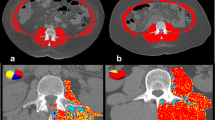

Potential mechanisms of sarcopenia due to impaired protein synthesis in cirrhosis and targeted interventions. Data compiled from OPTN / SRTR 2009 Annual Data Report. HHS/HRSA/HSB/DOT. http://optn.transplant.hrsa.gov/ar2009/data_tables_section9.htm